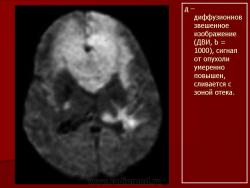

ГМ. Онк. Лимфомы головного мозга. Набор изображений. +

Лимфомы головного мозга.